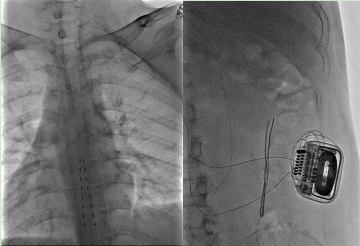

SCS 手术如同为身体安装一个「智能神经稳压器」。医生在影像引导下,将细如发丝的电极精准植入患者胸段脊髓的硬膜外腔,连接至皮下植入的刺激器。该装置持续释放微弱电脉冲,旨在「拦截」错误的疼痛信号,并调节过度兴奋的交感神经,从而从根源上改善胃肠功能与疼痛。

手术分两期进行。令人振奋的是,在第一期测试阶段,李先生的腹痛、恶心呕吐等症状便得到显著缓解,这证实了治疗靶点的准确性。随后,他顺利接受了永久刺激器植入。